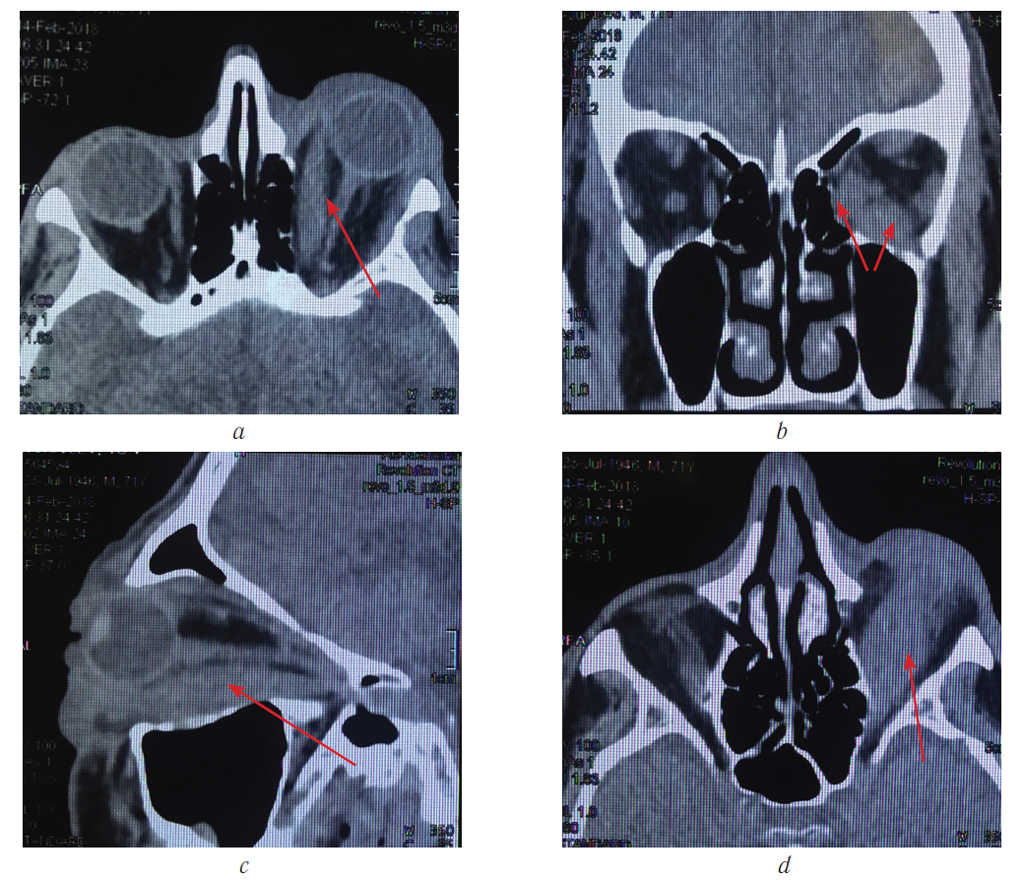

Резко увеличенные нижняя и внутренняя прямые мышцы визуализированы на компьютерных томограммах (рис. 3).

Рис. 3. Компьютерные томограммы орбит того же больного (во всех проекциях визуализируются увеличенные нижняя и внутренняя прямые мышцы (указаны стрелкой); c — визуализируется увеличенная нижняя прямая мышца на всём протяжении от зоны прикрепления к склере до сухожильного кольца

Fig. 3. Computer tomograms of patient’s orbits (in all projections, enlarged lower and inner rectus muscles are visualized (indicated by an arrow); с — an enlarged lower straight muscle is visualized from the attachment zone to the sclera to the tendon ring